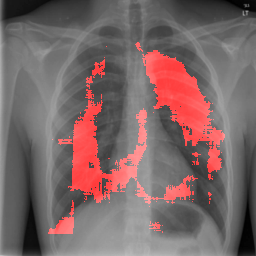

4.2.2 Pulmonary Edema Localization

In order to test the effectiveness of the localization procedure in areas other than the heart region, we chose pulmonary edema which occurs in the lung region. Also, pulmonary edema is detected by the net like white structure in the lung area. No anatomical shape change is associated with the abnormality. We have found that the localization is obtained best when the ROIs of lungs are taken to compute the map. Following the scheme in section 3.4, localization experiment on pulmonary edema is performed as shown in Fig. 8. It has been observed that the classifier is not sensitive to the fine features like septal or Kerley B lines. The localization is mainly obtained in the lung region where excess fluid is observed. Some localization regions are outside the lung region which occurs primarily for the fact that, even though the occlusion center is outside the lung, it occludes lung region and thus the probability drop occurs.

In a similar fashion, additional localization results for Pulmonary Edema is shown in Fig. 13. In Fig. 13(a) and (b) localization of two examples of CXRs with Pulmonary Edema is shown. As stated earlier the classifier localizes in the lung region. This is not the case when normal images are used to localize Pulmonary Edema as seen in Fig. 13(c) and (d). The localizations are obtained in random dense locations such as the sternum or heart. Like the cardiomegaly case, the histogram averages for CXRs with pulmonary Edema (Fig. 13(e)) shows a sensitivity toward pulmonary edema detection while the normal CXRs shows a spread out detection. It is interesting to note that, in the histogram of normal images high probability (¿0.85) is non-existent, thus ensuring low false positive rate. In the test set none of the normal images have been diagnosed as Pulmonary Edema. The failure cases are shown in Fig. 12. These CXRs are with Pulmonary Edema. However, the localization algorithm shows that one of them localizes in lungs whereas the other one shows a localization pattern similar to that obtained in normal CXRs.